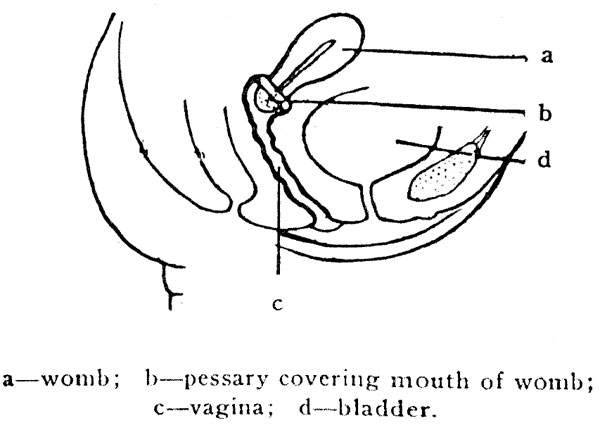

Follow the directions given with each box, and learn to adjust it correctly; one can soon feel that it is on right. After the pessary has been placed into the vagina deeply, it can be fitted well over the neck of the womb. One can feel it is fitted by pressing the finger around the soft part of the pessary, which should completely cover the mouth of the womb. If it is properly adjusted there will be no discomfort, the man will be unconscious that anything is used, and no germ or semen can enter the womb.

a—womb; b—pessary covering mouth of womb; c—vagina;

d—bladder.

a—womb; b—pessary covering mouth of womb; c—vagina;

d—bladder.